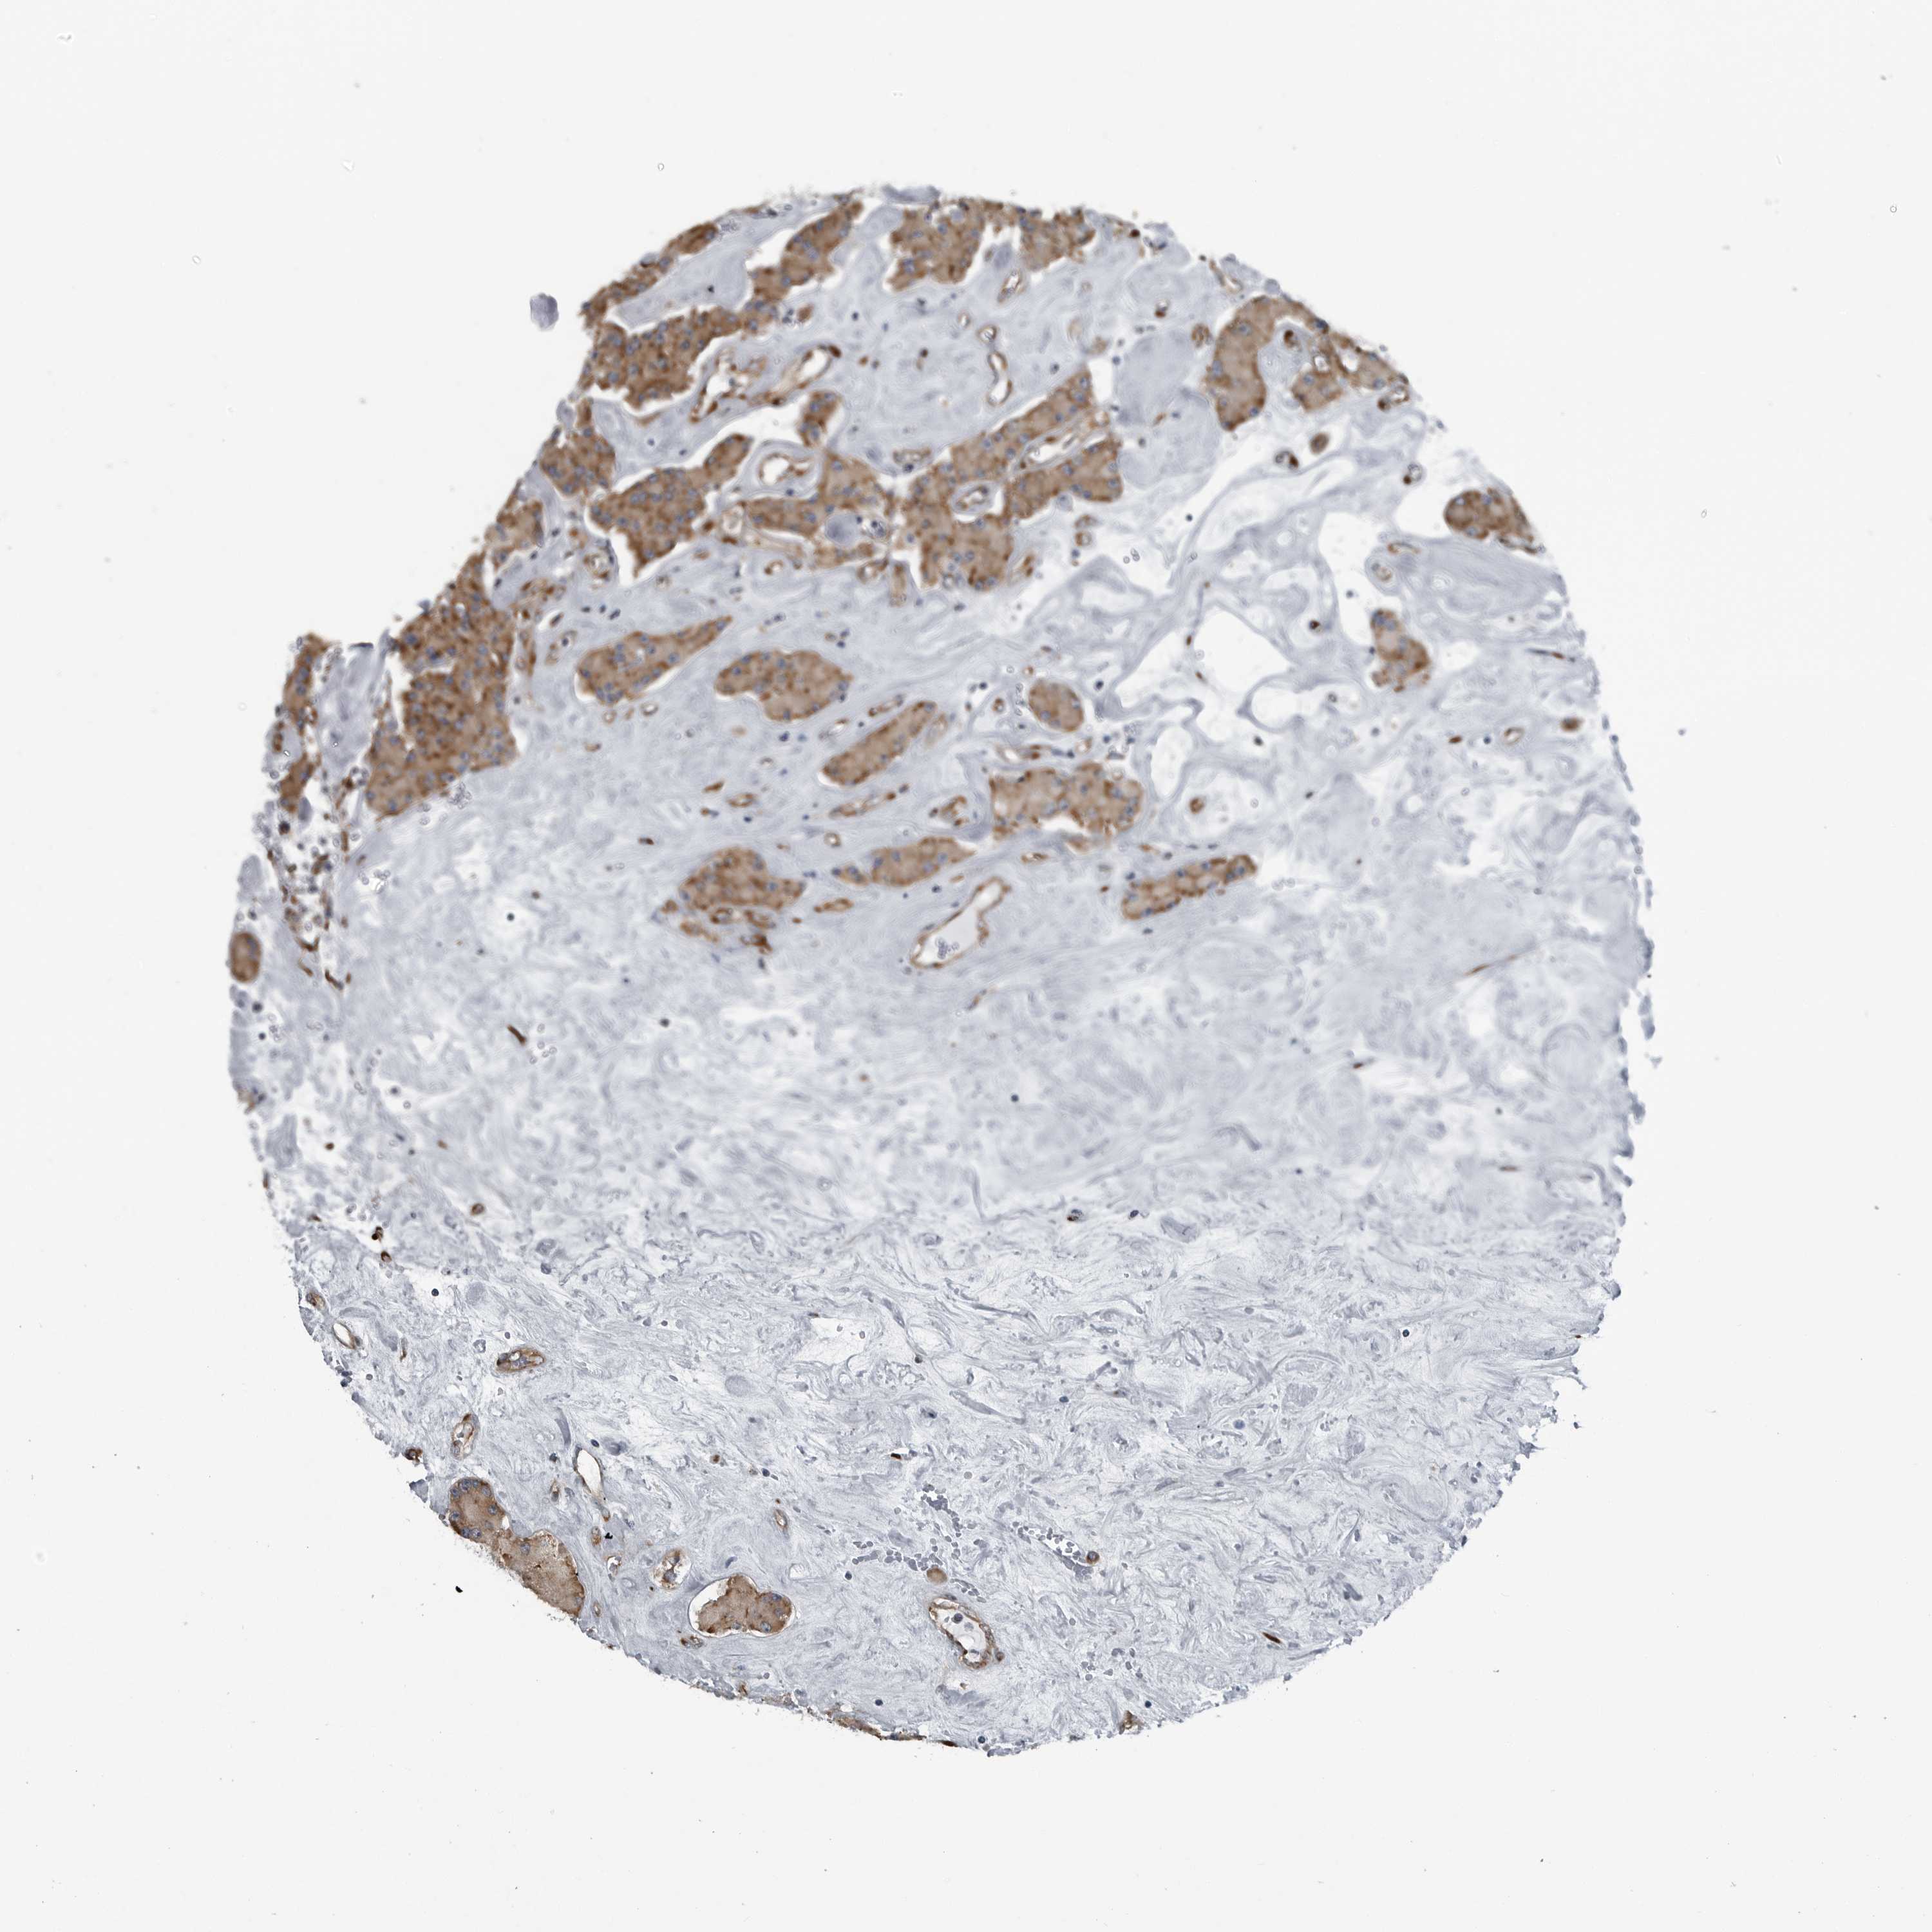

CEP85